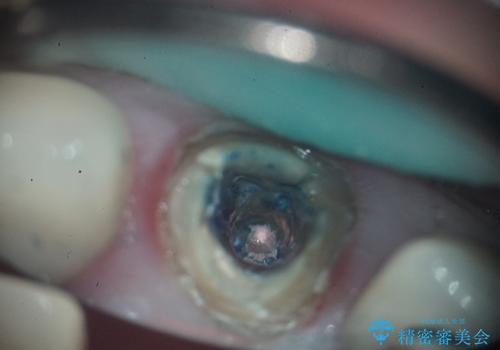

- 治療計画

- 前歯の痛みと破折を主訴にご来院されました。精密な診査の結果、歯の根元までひび割れが進行し、保存が困難であると診断。見た目にも関わる前歯を失うことへの患者様の不安を考慮し、抜歯と同時にインプラントを埋入する抜歯即時埋入インプラントによる治療計画を立案しました。これにより、歯がない期間を最小限に抑え、治療期間と身体への負担を軽減しながら、審美性の高い新しい歯を獲得することを目指します。

今回の治療では、まず原因となっていた前歯を慎重に抜歯し、その直後にインプラントを埋入しました。抜歯即時埋入は、歯を失うのとほぼ同時に新しい歯の土台を確保できるため、骨の吸収を防ぎ、仕上がりの美しさを保つ上で非常に有効です。また、治療当日に仮歯を装着することで、歯がない期間をなくし、患者様の精神的なご負担にも配慮しました。最終的に、周囲の歯と調和したオーダーメイドのセラミッククラウンを装着。機能性だけでなく、天然歯と見分けがつかないほどの自然で美しい前歯を取り戻していただけました。